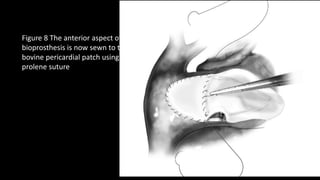

Figure 8 The anterior aspect of

bioprosthesis is now sewn to the

bovine pericardial patch using 4-0

prolene suture